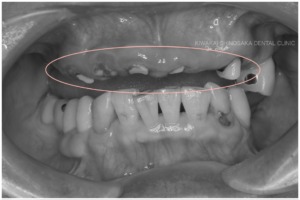

総義歯を作製するにあたり、複数の残根歯、特に左上に不都合な高さの歯が残っていることが懸念点でした。

(残根歯とは、虫歯や外傷などによって歯の頭の部分が失われ、歯の根だけが歯茎に残っている状態の歯のことをいいます。)

「できれば歯を抜かずに残したい」という患者さまのご意向にお応えし、抜歯は行わず、義歯に影響しないくらいの高さまで調整するだけにとどめた後、上顎用総義歯を作製いたしました。幸い、他の歯や歯周組織に影響を及ぼすほどの虫歯にはなっていなかったため、残根歯は全て抜かずにそのまま残すことができました。

| 治療内容 | 義歯をうまく適合させるために、残根歯の高さを調整しました。その後、義歯のおおまかな型取りを行い、患者さまのお口に合ったオーダーメイドのトレーを作製しました。 作製したトレーにて、シリコン印象剤による、患者さまのお口の機能を精密に反映した型取りを行い、最終のイメージを試適していただきました。 そこで審美性や機能性を確認し、最終の義歯に反映させ、完成となります。 |